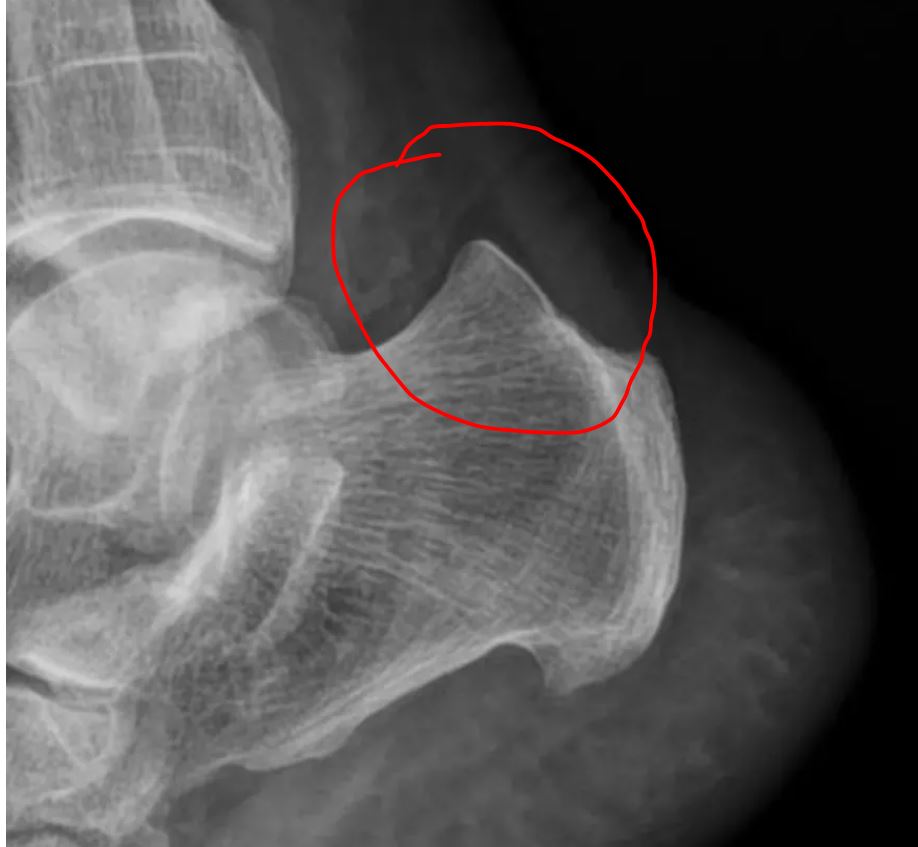

跟腱钙化是肌腱钙盐沉积导致,钙化的跟腱在X光下会表现为高亮度,和骨骼的亮度是相接近的。如果患者长时间进行剧烈运动,或进行繁重体力劳动等,都容易反复牵拉跟腱部位的胶原纤维,从而引起局部组织韧带损伤,出现跟腱钙化。在出现跟腱钙化后,可能表现为不能长时间站立、走路疼痛、跟腱水肿等症状

。